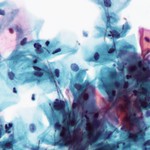

Imaxe ao microscopio de células infectadas co virus do mono

Imaxe de células infectadas cun virus

NIAID Integrated Research Facility. Mpox virus (CC BY-SA)